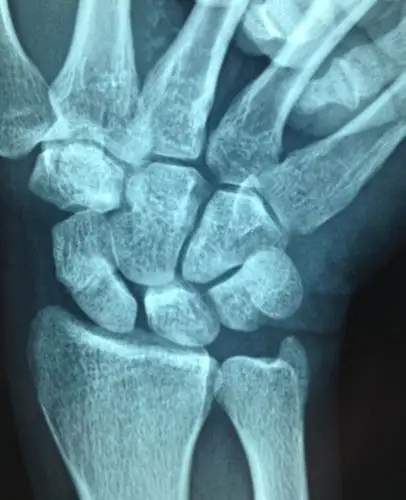

左手手腕舟骨骨折,这受伤程度严重吗?目前已夹板固定敷药8天.